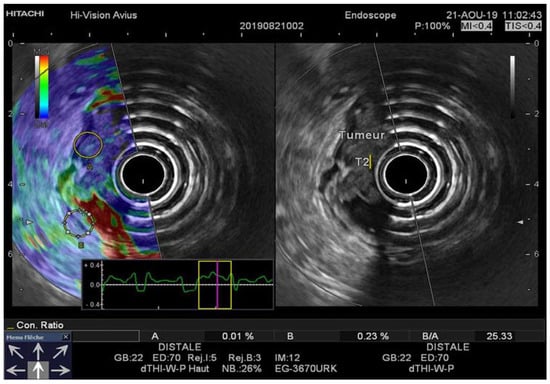

Figure 3. (A) EUS-RTE aspect in a 67-year-old female with pT3 rectal cancer. (B) EUS aspect of the same tumor. The tumor was classified as T3 with the cutoff value strain ratio (B/A) of 46.66. T3 was confirmed by histopathologic examination after surgical resection. RTE, real-time elastography.